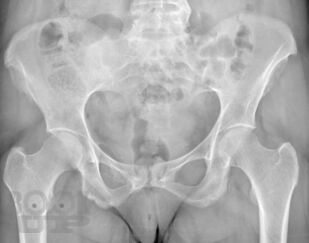

В учебном пособии представлены основные сведения о ревматологических заболеваниях, которые протекают с поражением суставов кисти, подробно изложена их рентгенологическая семиотика, описаны диагностические возможности других методов лучевой диагностики, таких как ультразвуковая диагностика, магнитно-резонансная и компьютерная томография. Особое внимание уделено дифференциальной диагностике заболеваний кисти.